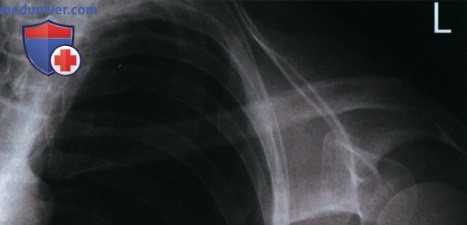

Рекомендации по анализу рентгенограмм (рис. 1):

РИСУНОК 1 Рентгенограмма ключицы в ПЗ проекции: правильное положение.

• Медиальный конец ключицы находится вблизи латерального края позвоночного столба (рис. 3 и 4)

• Ключица и верхний угол лопатки визуализируются на одном поперечном уровне (рис. 5 и 6)

• Середина ключицы находится в центре экспозиционного поля

• В экспозиционное поле входят ключица и акромиальный отросток

а) Поворот туловища в противоположную сторону от исследуемой ключицы. На рентгенограмме ключицы в ПЗ проекции выявить ее ротацию и продольное проекционное укорочение можно, сравнив положение медиального конца ключицы и позвоночного столба. Если туловище отвернуто от исследуемой ключицы, то ее медиальный конец будет накладываться на позвоночный столб (рис. 3).

б) Поворот туловища в сторону исследуемой ключицы. Если при рентгенографии ключицы в ПЗ проекции туловище повернуто к исследуемой ключице, на рентгенограмме медиальный конец ключицы будет отодвинут от позвоночного столба, а сама она будет подвергаться продольному проекционному укорочению (рис. 4).

в) Наклон верха срединной коронарной плоскости вперед. Если при рентгенографии ключицы в ПЗ проекции верх срединной коронарной плоскости наклонен вперед, на рентгенограмме верхний угол лопатки будет визуализироваться выше ключицы (рис. 4).

г) Наклон верха срединной коронарной плоскости назад. Если при рентгенографии ключицы в ПЗ проекции верх срединной коронарной плоскости наклонен назад, на рентгенограмме верхний угол лопатки будет визуализироваться ниже ключицы (рис. 5).